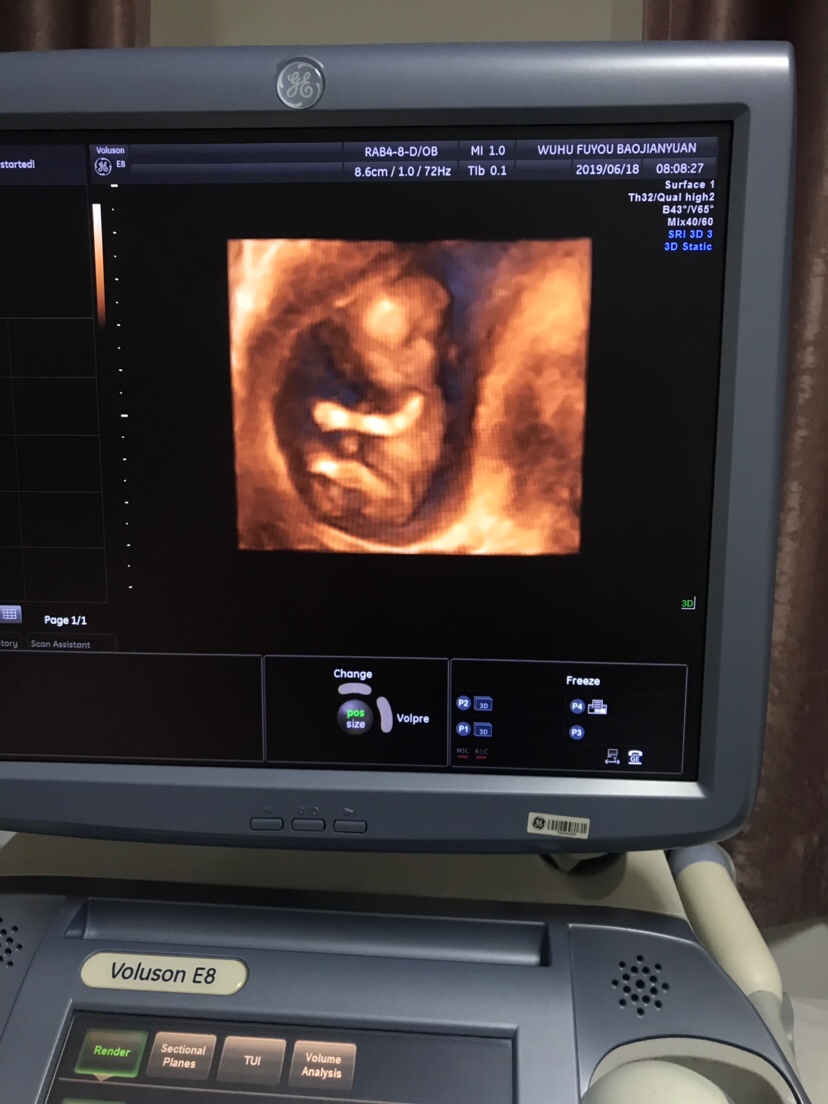

可乐双胞胎兄弟

2018-06-01

2736 人回复